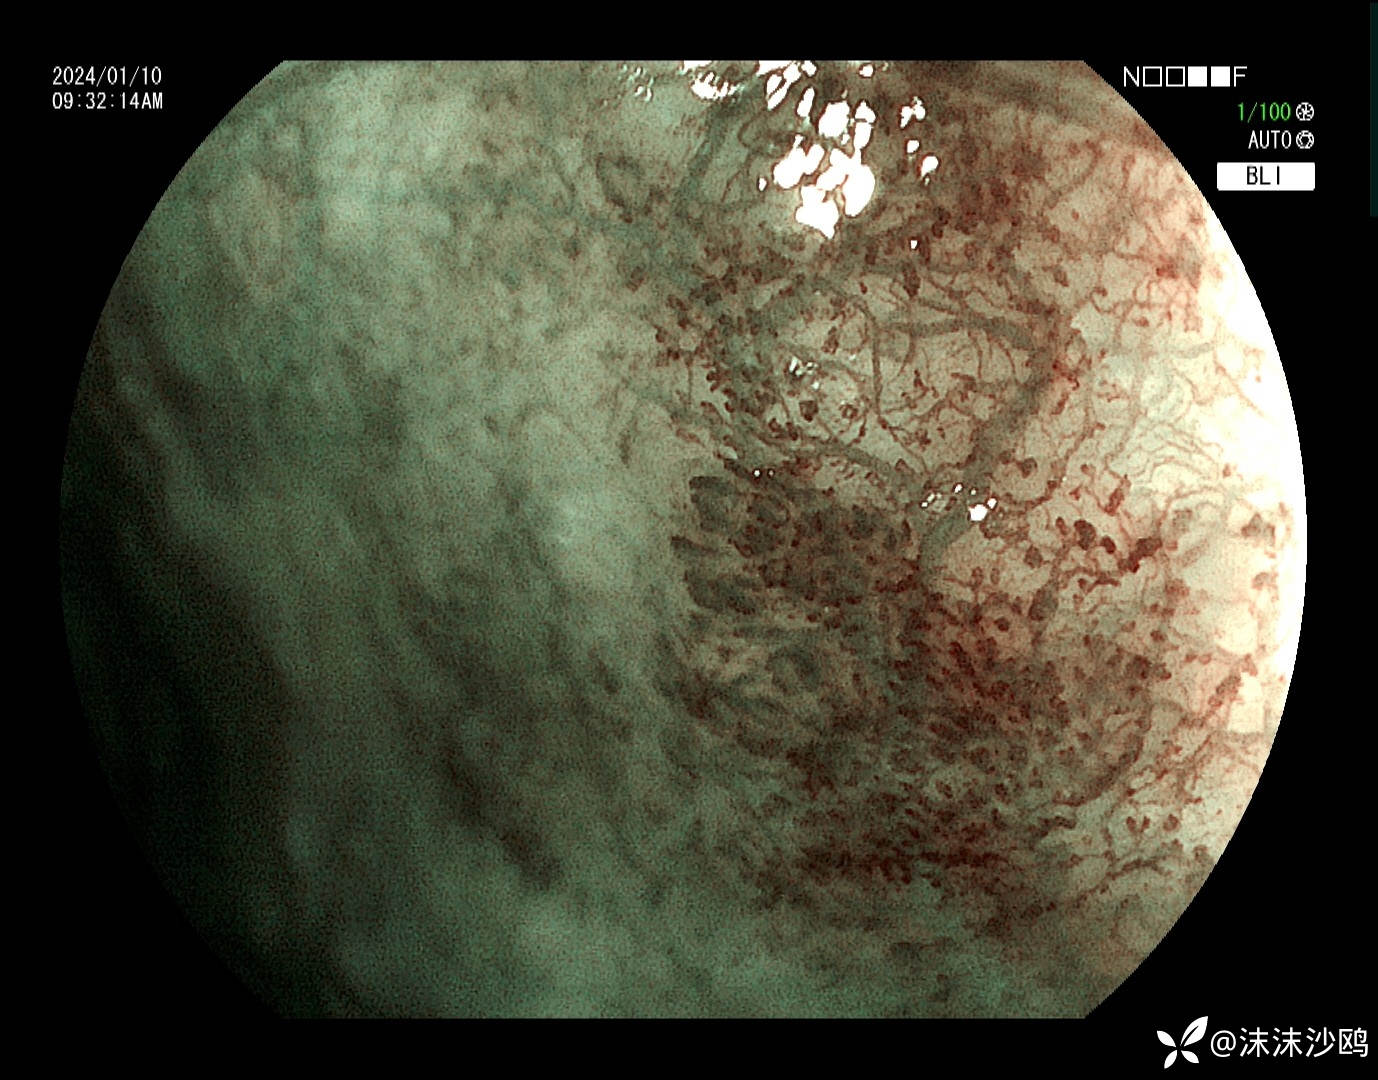

今天的,做了放大,但我们没有碘染色剂,所有没做碘染。

后三次都是我做的,因为今天对比了病灶,感觉变化不明显,没有取病检。